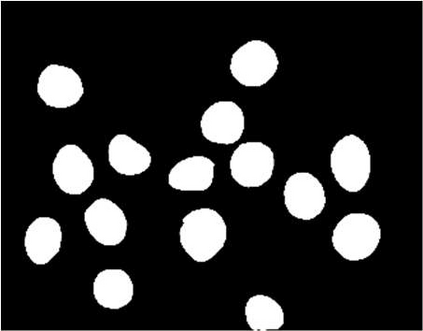

Multiple myeloma cancer is a type of blood cancer that happens when the growth of abnormal plasma cells becomes out of control in the bone marrow. There are various ways to diagnose multiple myeloma in bone marrow such as complete blood count test (CBC) or counting myeloma plasma cell in aspirate slide images using manual visualization or through image processing technique. In this work, an automatic deep learning method for the detection and segmentation of multiple myeloma plasma cell have been explored. To this end, a two-stage deep learning method is designed. In the first stage, the nucleus detection network is utilized to extract each instance of a cell of interest. The extracted instance is then fed to the multi-scale function to generate a multi-scale representation. The objective of the multi-scale function is to capture the shape variation and reduce the effect of object scale on the cytoplasm segmentation network. The generated scales are then fed into a pyramid of cytoplasm networks to learn the segmentation map in various scales. On top of the cytoplasm segmentation network, we included a scale aggregation function to refine and generate a final prediction. The proposed approach has been evaluated on the SegPC2021 grand-challenge and ranked second on the final test phase among all teams.